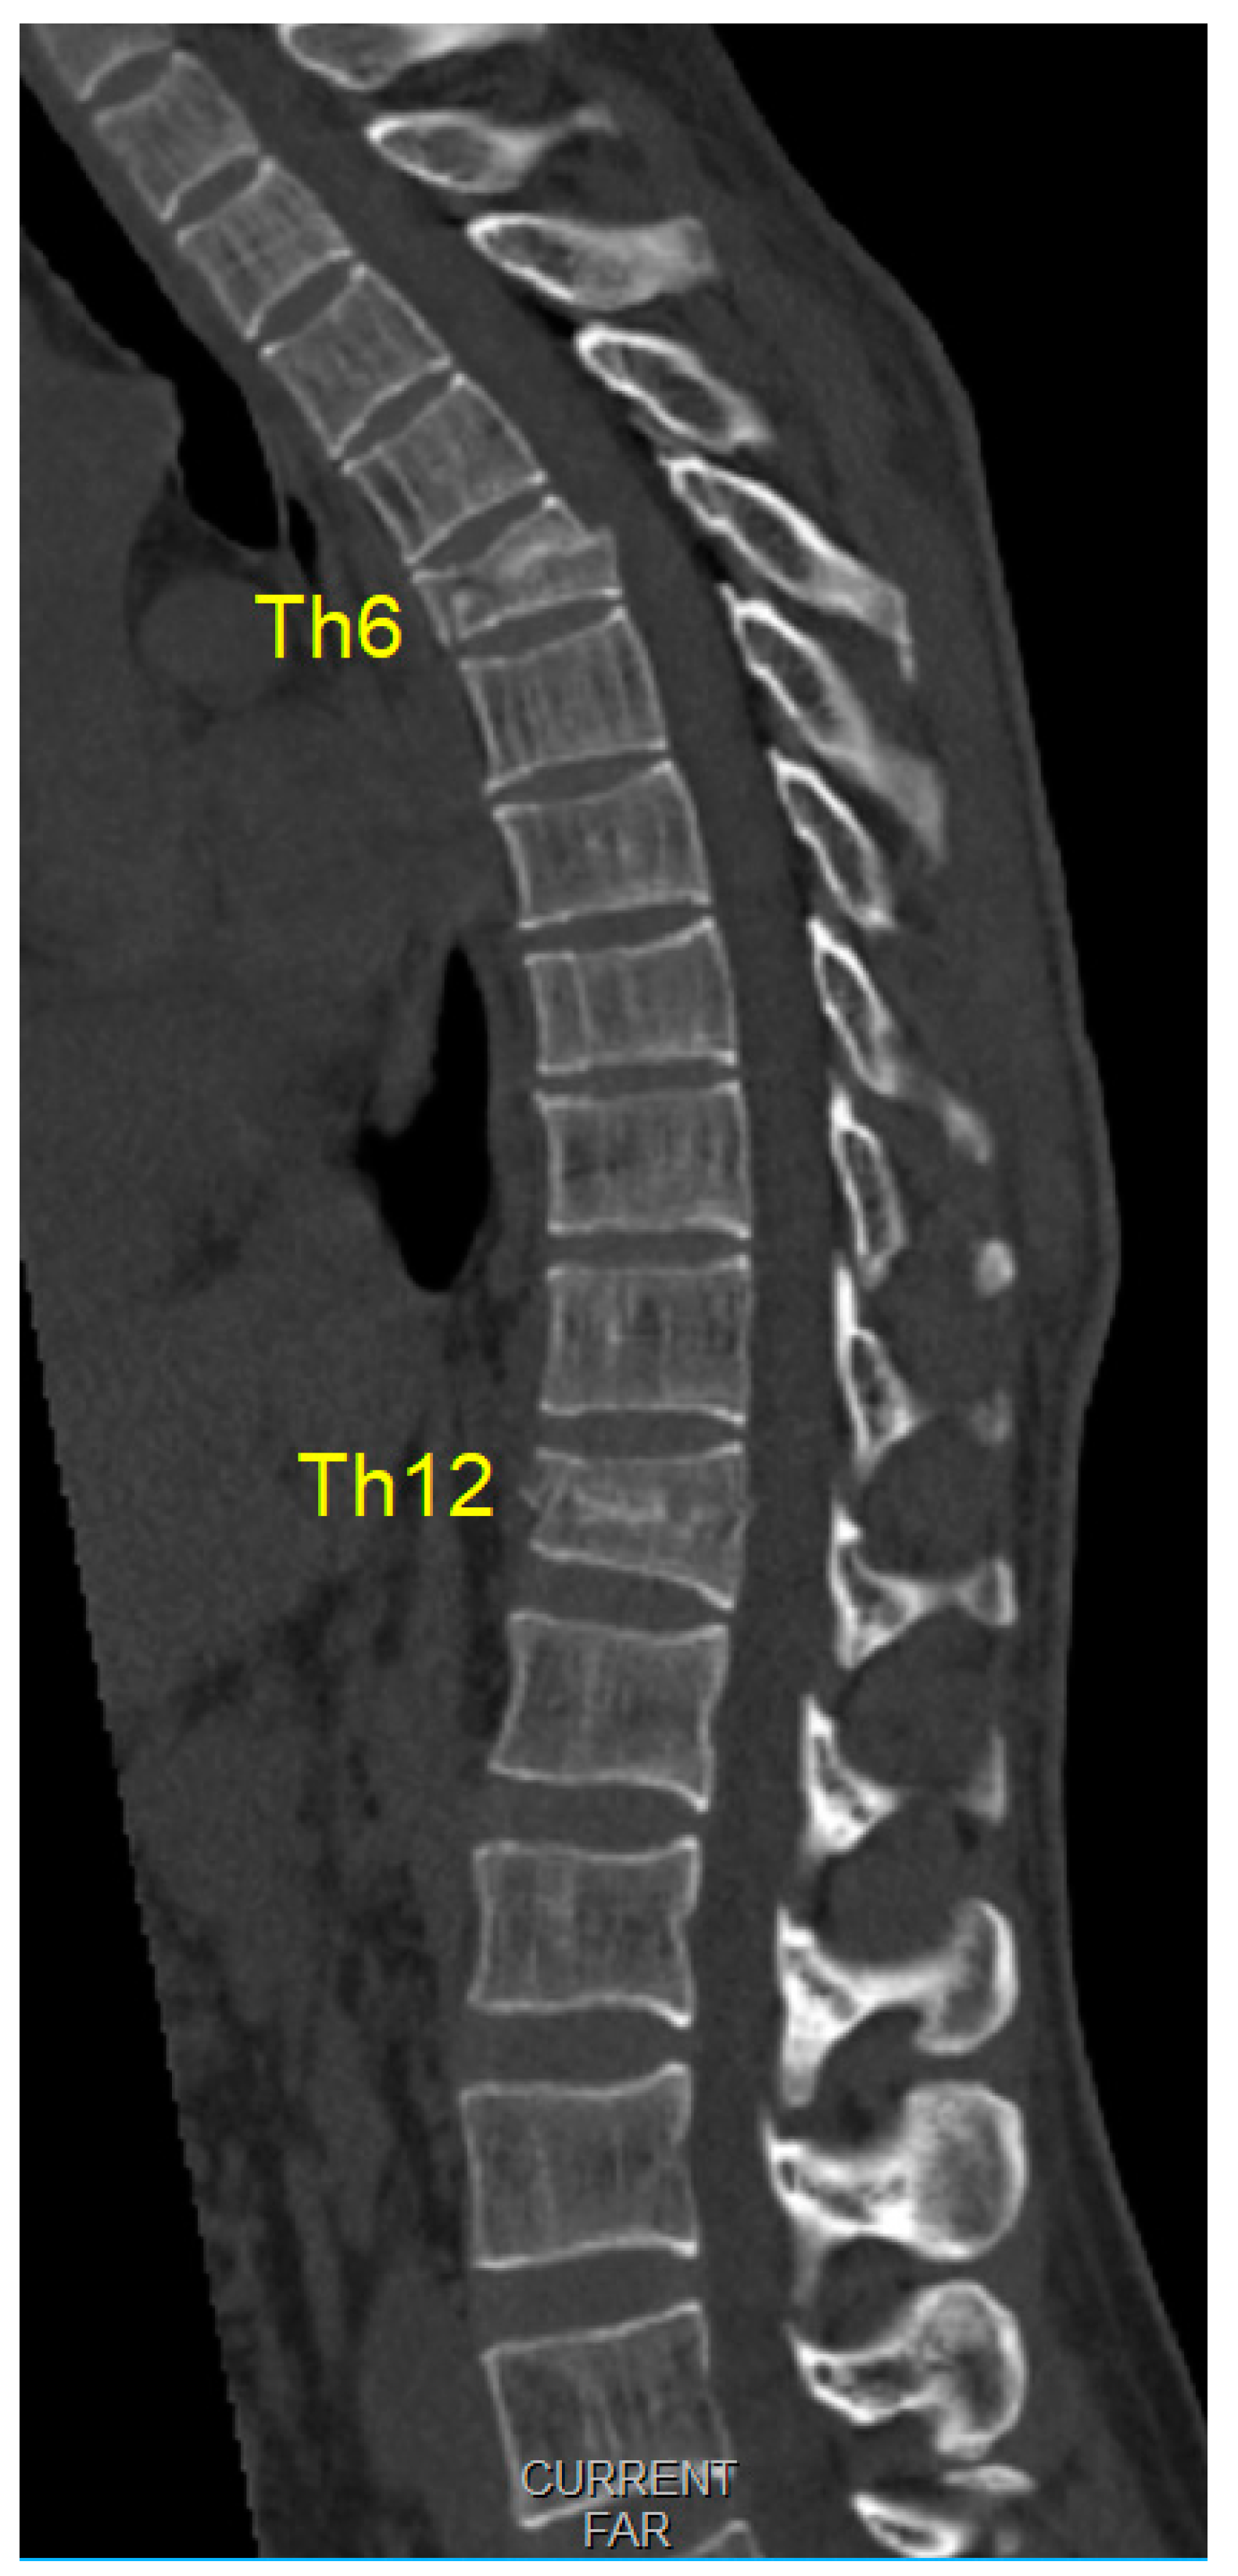

2. Case Report